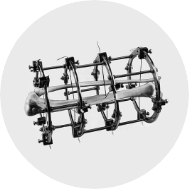

جراحات الإطالة وجراحة العظام

صبحت جراحات تطويل القامة و علاج قصر القامة من الأمور الشائعة فى جراحة العظام. فبعض المرضى يعانون من نقص طولهم مما قد يكون له أثر كبير على عملهم و على صحتهم النفسية و على ممارسة حياتهم اليومية. لذلك، فمن الطبيعي أن الناس يطمحون دائما لإضافة بضع سنتيمترات لزيادة طول قامتهم. كما ان هناك مرضى يعانون من وجود فرق فى الطول بين الساقين مما يؤدي الى صعوبة فى المشي و الام فى أسفل الظهر و العرج